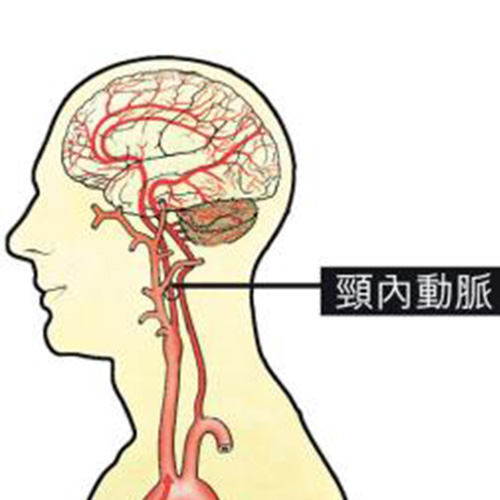

腦梗塞圖片

腦梗塞的注意事項圖

腦梗塞講解

患腦梗塞之後的症狀表現